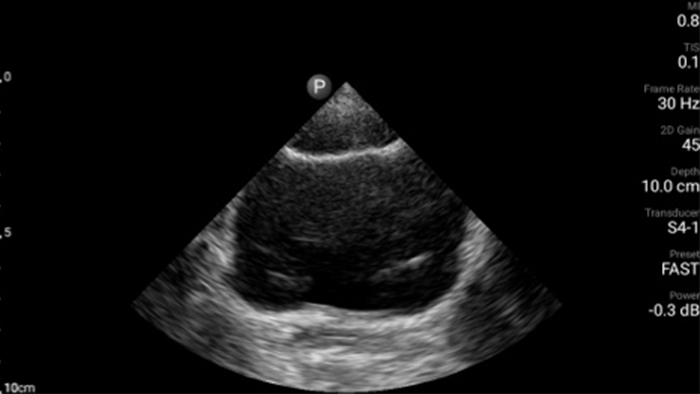

Exceptional ultrasound imaging

Lumify handheld ultrasound offers images that enhance diagnostic confidence.

See more when it counts

Lumify can help you make real-time decisions with more confidence, from assessment to recovery. Reveal the subtle details of an image, uncover enriched tissue definition with multiple angles and much more.

Emergency medicine